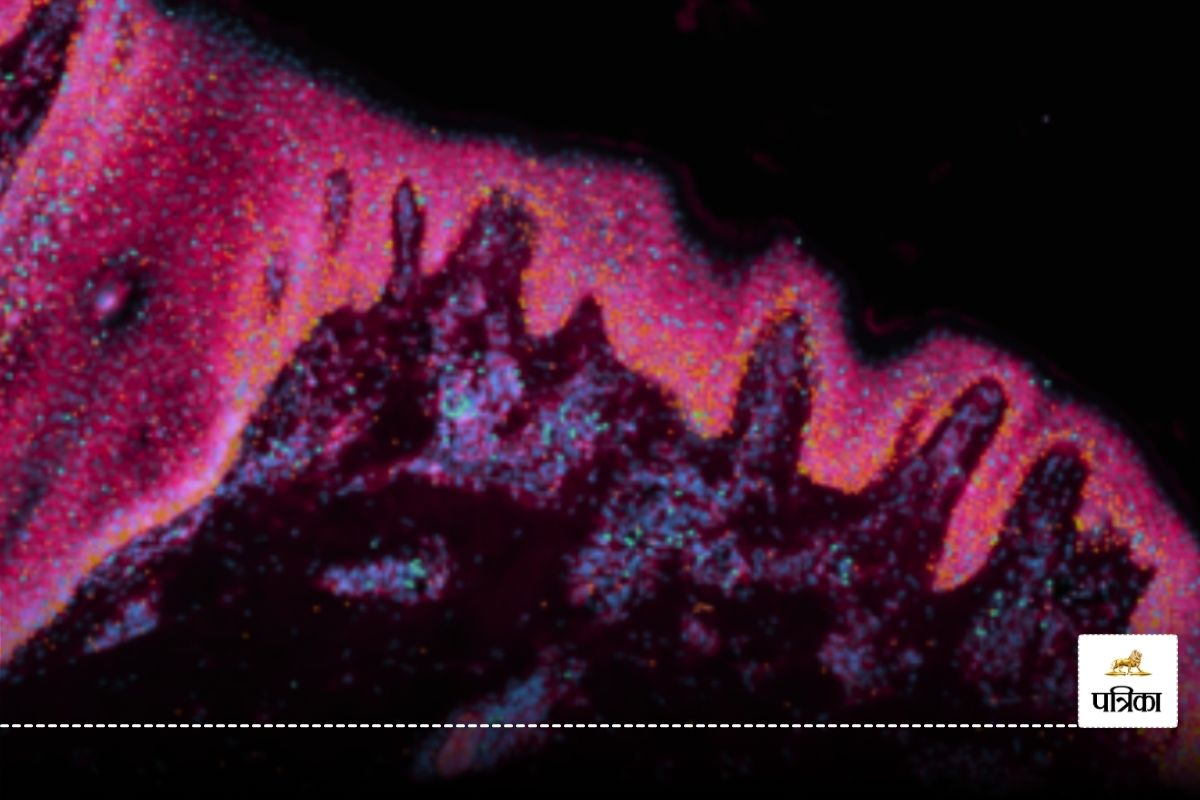

नेचर जर्नल में प्रकाशित अध्ययन के मुताबिक शोधकर्ताओं ने नक्शे में मानव त्वचा के जटिल विकास और बालों के रोम पैदा होने का चित्रण किया। इसके लिए जीनोमिक तकनीकों का उपयोग किया गया। शोध मानव त्वचा के निर्माण के लिए नया रास्ता खोल सकता है। शोध की सह-प्रथम लेखिका डॉ. एलेना विन्हेम ने कहा कि त्वचा और बाल प्रत्यारोपण के क्षेत्र में क्रांतिकारी बदलाव आ सकते हैं। जन्मजात त्वचा विकारों पर अनुसंधान के नए रास्ते खुलेंगे।

शोध दल ने प्रयोगशाला में त्वचा भी विकसित की। यह बाल उगाने में सक्षम है। यह मानव जन्म से पूर्व की त्वचा से काफी मिलती-जुलती है। शोध से त्वचा में रक्त वाहिकाओं के निर्माण और प्रतिरक्षा कोशिकाओं के विकास के बारे में नई जानकारियां सामने आई हैं।